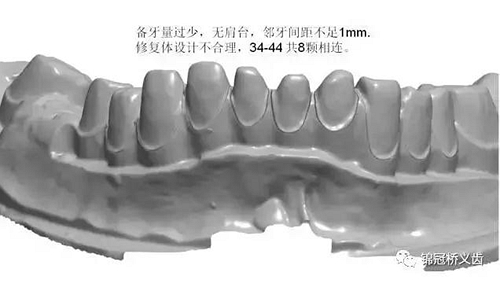

1、臨床備牙不合理或基牙條件不適合做氧化鋯

如:無肩臺、凹面肩臺、邊緣線不清晰、雙重邊緣線、備牙空間不足、基牙有倒凹或牙橋沒有共同就位道、基牙切端或頜緣過于尖銳等等。